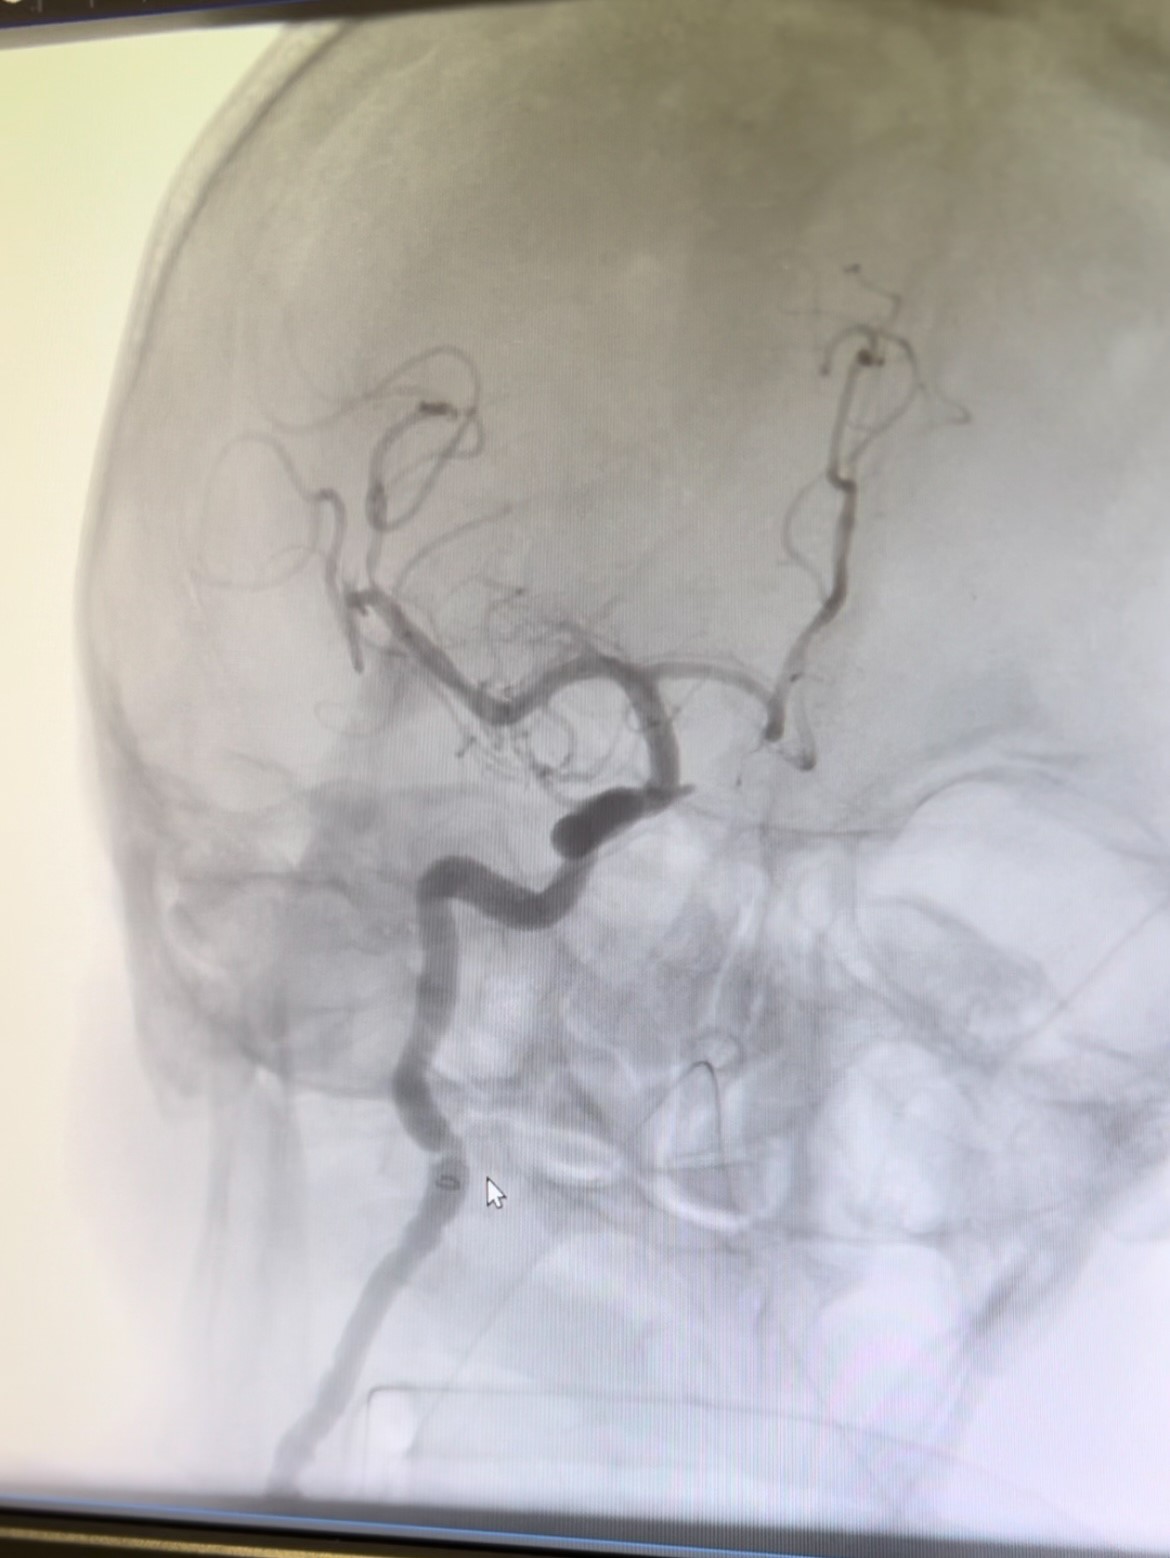

Yapılan işlem hakkında bilgi veren Girişimsel Nörolog- Doç. Dr. Ezgi Sezer Eryıldız, "Hastamız Yusuf Sezer, 68 yaşında. Bize inme semptomları sonrasında erken bir saatte ulaştı. Geldiğinde bilinç bozukluğu, konuşma bozukluğu ve bir tarafında güç kaybı gibi bulguları mevcuttu. Yaptığımız görüntüleme yöntemleriyle, hastamızın şah damarının tıkalı olduğunu tespit ettik. Hızla anjiyo ünitesine alarak trombektomi işlemini uyguladık. Başarılı geçen bu işlem sonrasında, hastamızda dakikalar içerisinde felce dair bulgular geriledi. Ardından, bu beyin damar tıkanıklığının neden geliştiğine dair gerekli incelemeleri yaptık ve hastamızın tedavisini düzenledik. Şu an hastamız, inme öncesindeki gibi yaşamına devam edebiliyor" dedi.